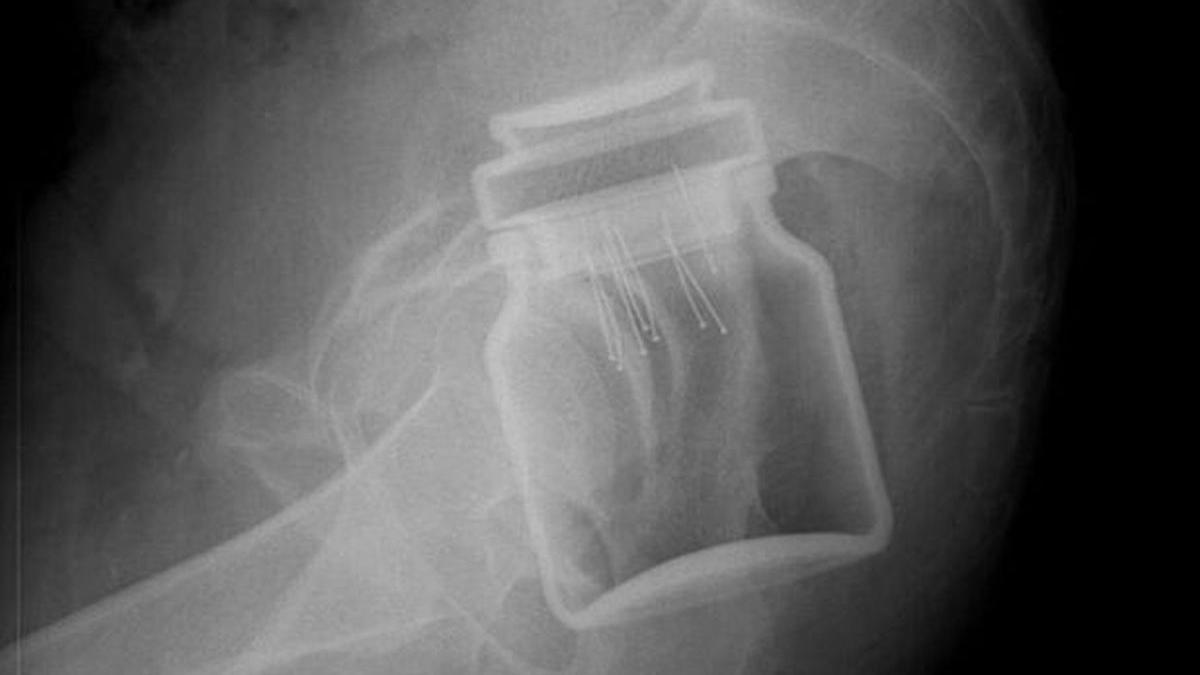

Un bărbat din Botoşani a ajuns la Urgențe cu un borcan în anus: Eu sunt ăla de anul trecut, cu paharul22 Mai